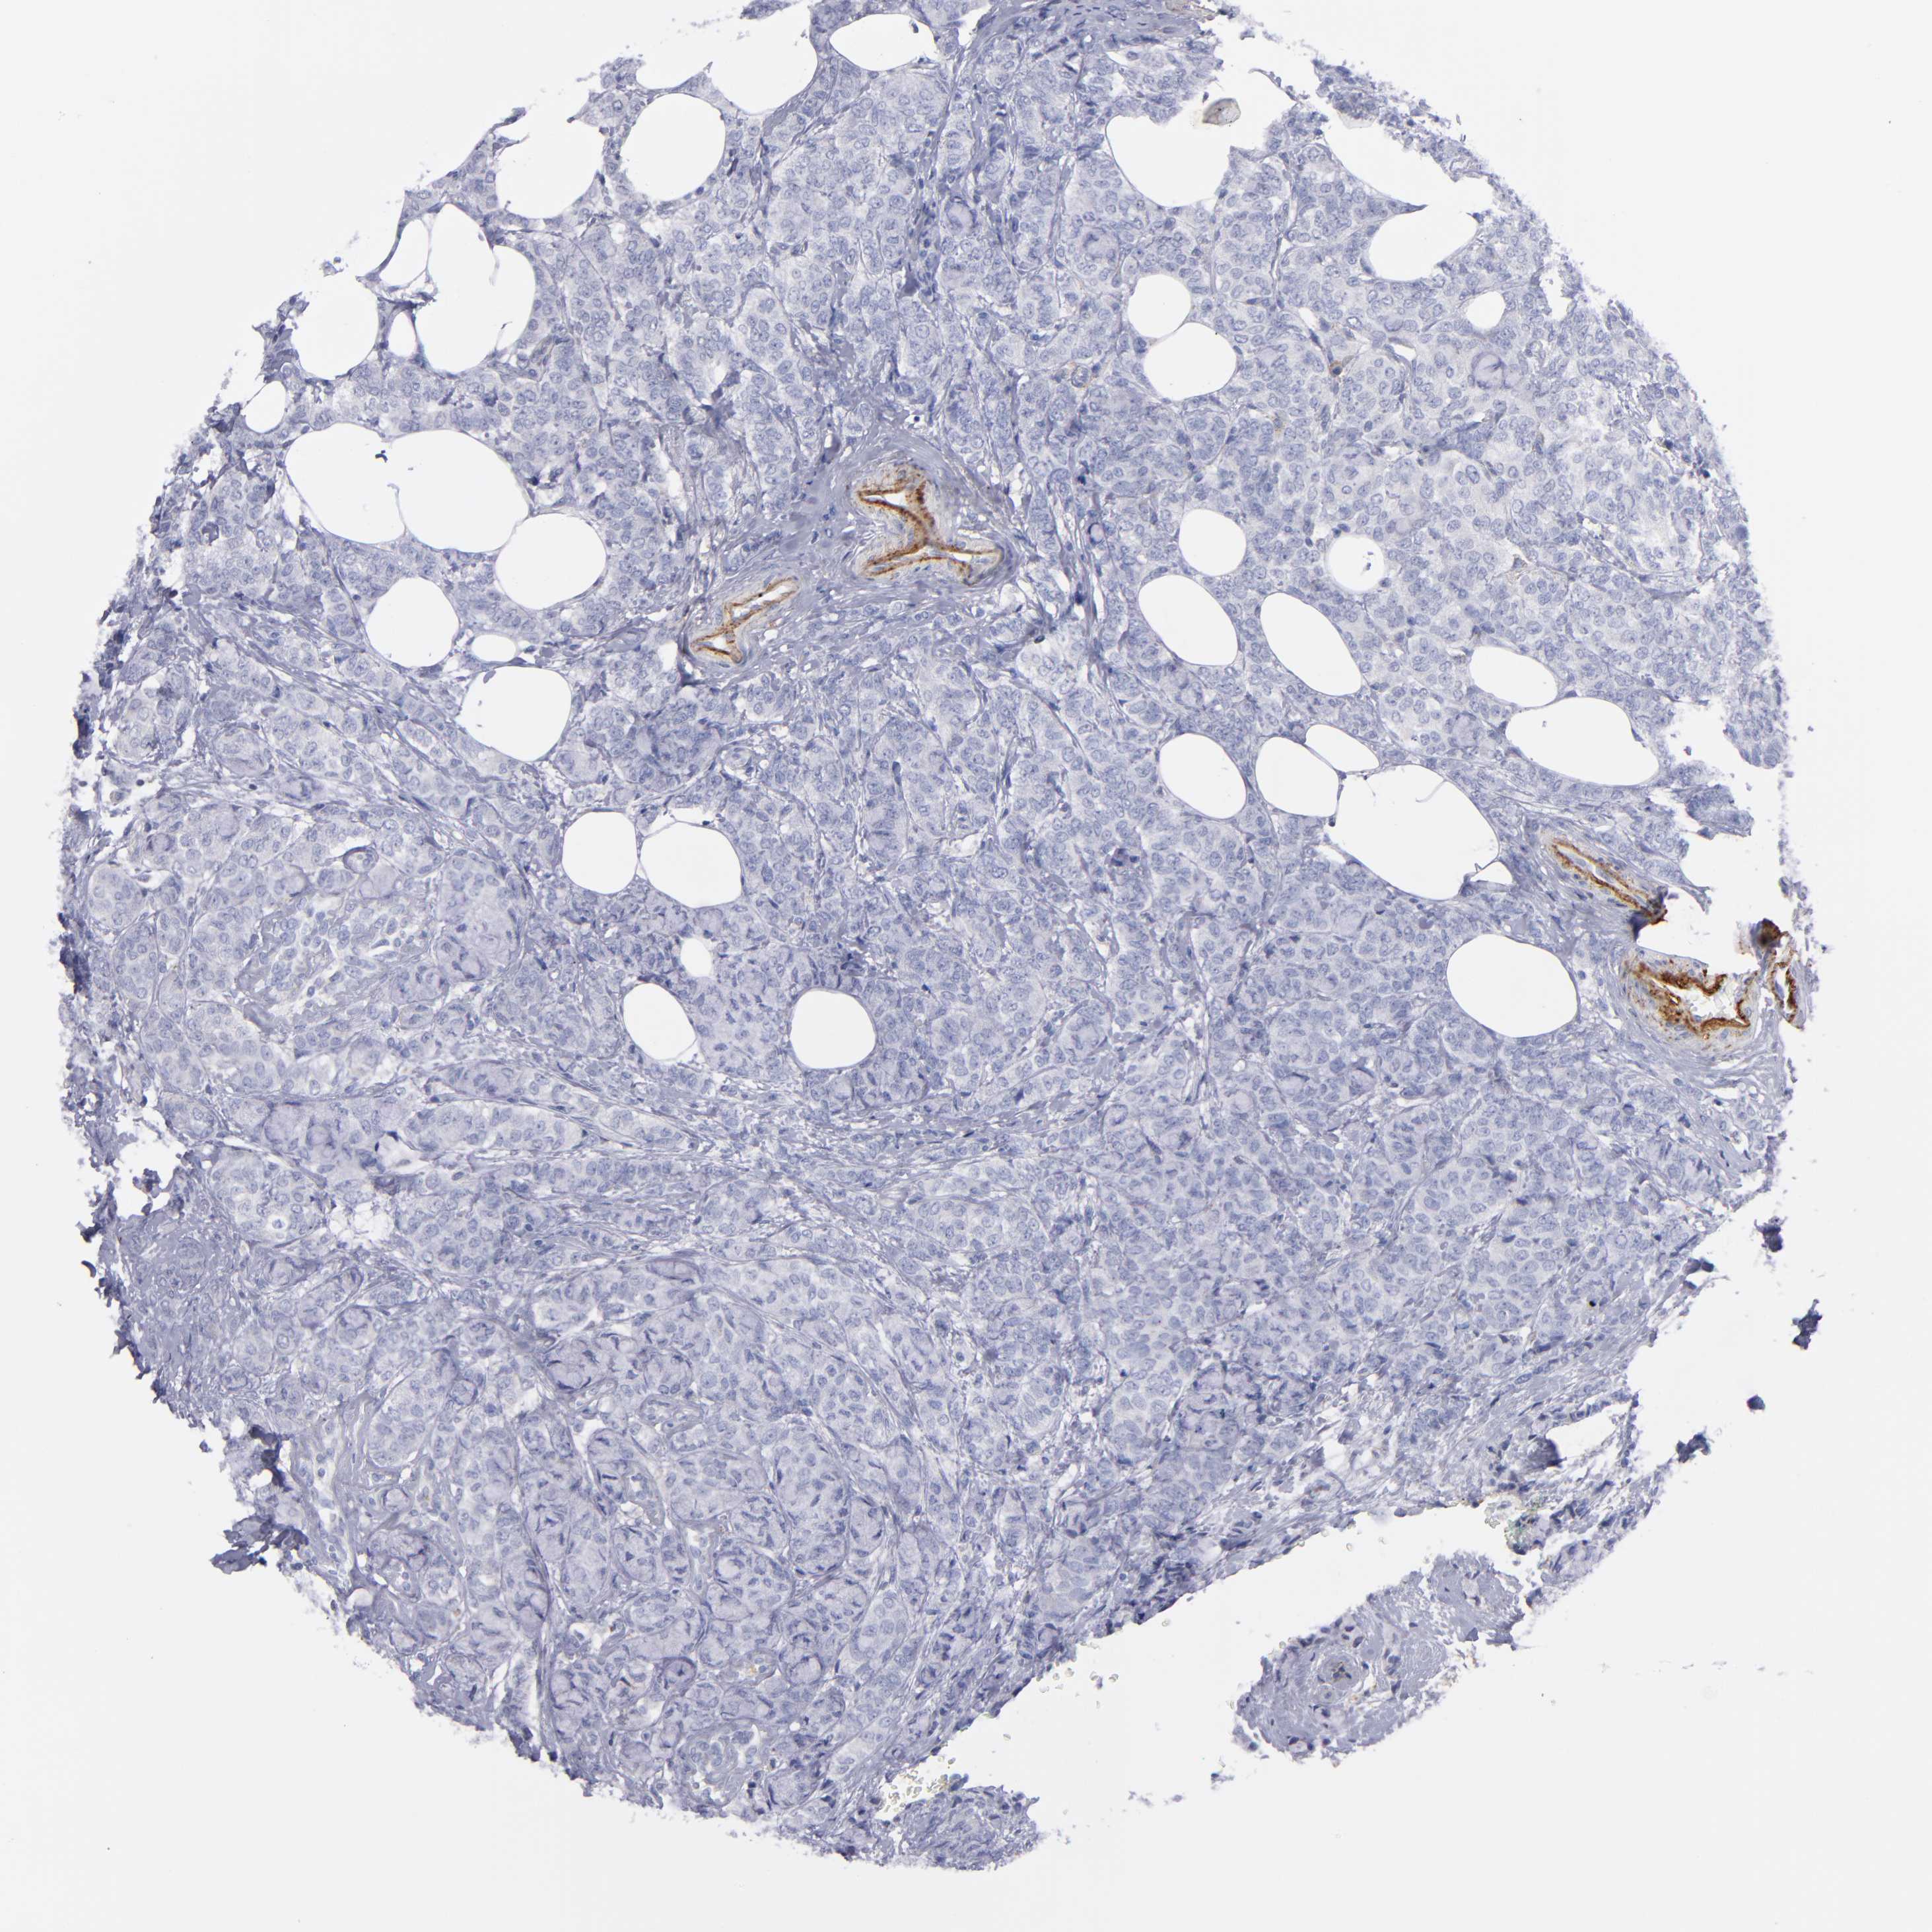

CANCER BREAST CANCER Show tissue menu

BRCA TCGA BRCA VALIDATION PROTEIN EXPRESSION